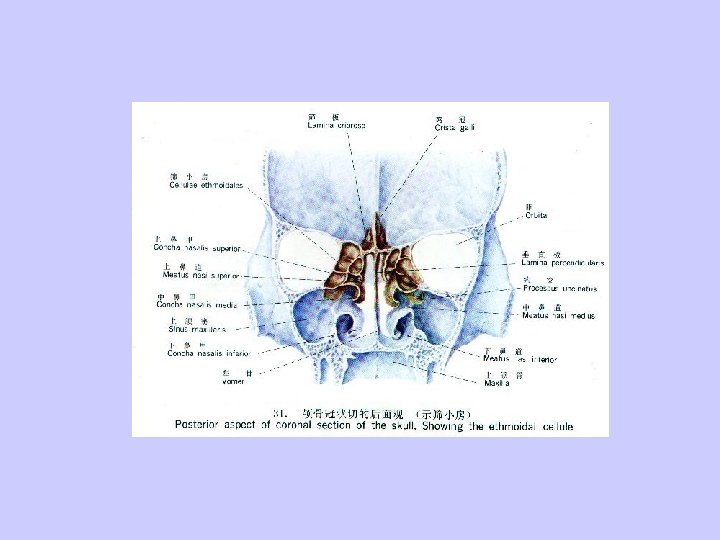

Sinusitis Acute suppurative sinusitis Features of sinus anatomy: 1、small ostia of the sinuses; 2、continuative mucosa between nasal cavity and sinuses; 3、contiguous of the ostia; 4、location of the astia and features of the sinuses.